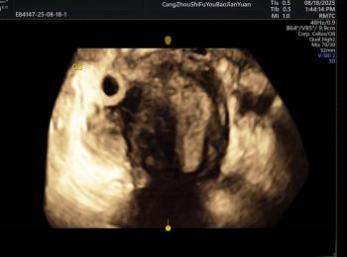

孕早期“精准监测”,化解潜在风险

早期妊娠是母婴健康的关键阶段,超声检查作为常用监测方式,能多角度观察孕囊与子宫角肌层的关系,辅助医生判断孕囊着床位置,精准区分间质部妊娠与宫角妊娠,为及时干预、保障孕早期安全提供重要依据,让准妈妈们更安心度过孕期初期。

子宫三维成像诊断宫角妊娠